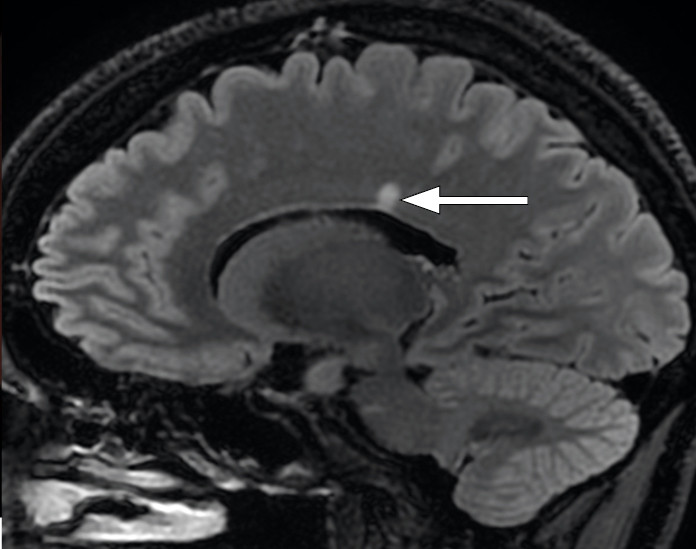

MRI of the head/orbits with contrast showed normal optic nerves and no signs of retrobulbar pathology. A periventricular hyperintensity with typical demyelinating features was seen (Figure 3), along with small, non-specific, rounded hyperintensities in frontal and parietal regions of the right hemisphere (Figure 3). None of the lesions were contrast-enhancing, which would have been a sign of active inflammation.

The periventricular hyperintense lesion seen on MRI suggested demyelinating disease. However, there was no sign of inflammation of the optic nerve, which would be expected in a case of demyelinating optic neuritis. A peripapillary infiltrate and cells in the vitreous could indicate ocular toxoplasmosis (2). However, there was no evidence on the MRI to suggest a Toxoplasma infection of the central nervous system, which would typically result in multiple contrast-enhancing lesions and perifocal oedema (4). We therefore suspected that the patient may have two conditions: an ocular toxoplasmosis, which would explain the symptoms, and an additional subclinical demyelinating disease.

Although the test results and treatment response both indicated that toxoplasmosis was the cause of the patient's symptoms, the findings on MRI strongly suggested that the patient also had a demyelinating disease. A lumbar puncture was therefore performed. Cerebrospinal fluid analysis revealed slightly elevated levels of protein at 0.58 g/L (reference range 0.15–0.50) and albumin at 515 mg/L (0–350), but a normal albumin index of 6.6 (0–9), IgG index of 0.56 (< 0.70) and cell count (< 5). Isoelectric focusing revealed oligoclonal IgG bands in the cerebrospinal fluid but not in the serum, indicating intrathecal IgG production. PCR testing for T. gondii was negative, as were antibody tests for IgM and IgG against B. burgdorferi.

This case history is an example of how a brain MRI can reveal signs of demyelinating disease in patients without clinical symptoms. This phenomenon, known as radiologically isolated syndrome, poses a significant therapeutic dilemma because about one-third of these patients will experience an episode of MS within five years (23). The presence of lesions in the spinal cord or oligoclonal IgG bands in the cerebrospinal fluid increases this risk significantly (24). Our patient did not fulfil the radiological McDonald criteria (dissemination in time and place) for multiple sclerosis, either initially or upon subsequent examination, and nor did she have spinal cord lesions. We chose therefore to continue with observation without initiating immunomodulatory therapy.